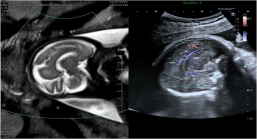

4D造影谐波成像技术(4D CHI):

1. 可应用于妇科领域,包括4D子宫输卵管造影;

2. 具备多切面显示功能,像观察CT片一样,更为全面了解病变的灌注情况。